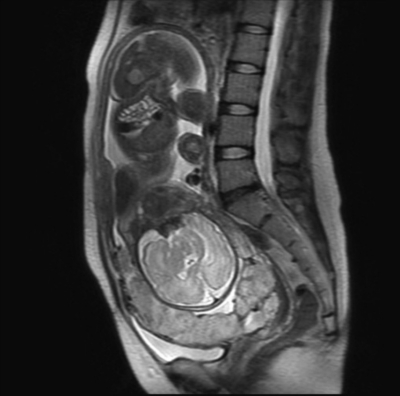

35歳の経産婦(3妊2産)。妊娠33週に周産期管理目的で、自宅近くの産科診療所から紹介され受診した。既往歴は、30歳時および32歳時に、それぞれ骨盤位および既往帝王切開の適応で選択的帝王切開。身長 156 cm、体重 56 kg 妊娠前体重 48 kg 。体温 36.8 ℃。脈拍 84/分、整。血圧 108/76 mmHg。現時点で自覚症状はなく、胎児心拍数陣痛図で異常を認めない。骨盤MRIのT2強調像を別に示す。

考えられるのはどれか。2つ選べ。

a. 前置血管

b. 前置胎盤

c. 癒着胎盤

d. 胎盤後血腫

e. 常位胎盤早期剝離